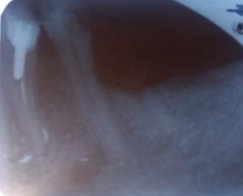

На верхней челюсти справа в районе зуба 6 образовалась небольшая припухлость, которая видна только со стороны щеки, при постукивании на сам зуб отдает болью, десна вокруг зуба не красная и не припухлая, воспаленной не выглядит, зуб залеченный.

Сделали снимок, врач, делавший снимок, направляет на удаление зуба по результатам снимка.

Возможно ли лечение этого зуба?